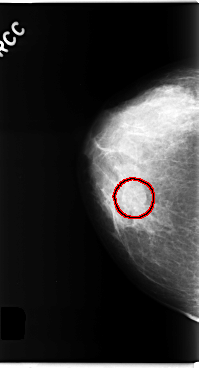

C_0284_1.RIGHT_MLO

RIGHT_CC LINES 4784 PIXELS_PER_LINE 2576 BITS_PER_PIXEL 12 RESOLUTION 50 OVERLAY

FILE: C_0284_1.RIGHT_CC.OVERLAY

TOTAL_ABNORMALITIES 1

ABNORMALITY 1

LESION_TYPE MASS SHAPE ROUND MARGINS OBSCURED

ASSESSMENT 3

SUBTLETY 4

PATHOLOGY BENIGN

TOTAL_OUTLINES 1

BOUNDARY